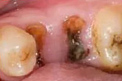

适应症状

• 残冠残根

• 根尖周炎

• 深龋蛀牙

• 牙髓坏死

根管治疗案例展示 TAIKANG BYBO DENTAL